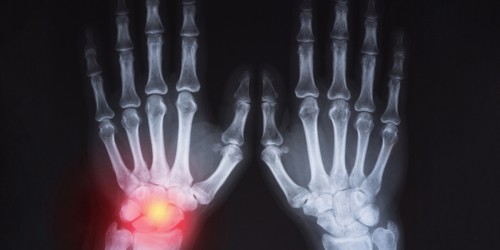

Lately, I have experienced pain and swelling (puffiness) towards the top middle of my right foot and there is also a hard boney lump behind this. I do not know whether the artificial joint is failing.